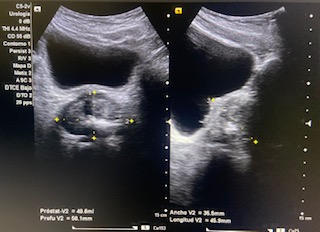

Volumen residual: 243 ml. Próstata de contornos regulares y ecogenicidad homogénea a simple vista. Volumen prostático: 49 cc.

En ecografía determinamos el tamaño de la próstata mayor de 20 cc, por tanto se trata de una HBP grado II. La medición del RPM nos permitió detectar que el paciente presentaba residuos elevados (243 ml).